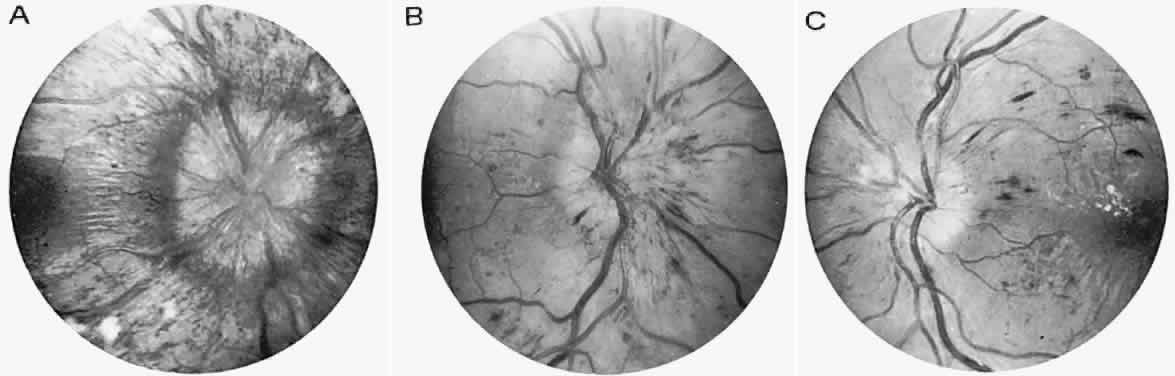

angiographic studies. Arch Ophthalmol 102:981, 1984 90. Newman NJ: Leber's hereditery optic neuropathy: new genetic considerations. Arch Neurol 50:540, 1993 91. Newman NJ, Lott MT, Wallace DC: The clinical characteristics of pedigrees of Lebers' hereditary optic neuropathy

causing intracranial hypertension without ventriculomegaly. Arch Neurol 48:740, 1991 180. Katz B: The dyschromatopsia of optic neuritis. Trans Am Ophthalmol Soc 93:685, 1995 181. Mojon DS, Rösler KM, Oetliker H: A bedside test to determine motion stereopsis using the Pulfrich phenomenon. Ophthalmol 105:1337, 1998 182. Selhorst JB, Saul RF: Uhthoff and his symptom. J Neuroophthalmol 15:63, 1995 183. Keltner JL, Johnson CA, Spurr JO et al: Visual field profile of optic neuritis: one-year follow-up in the optic